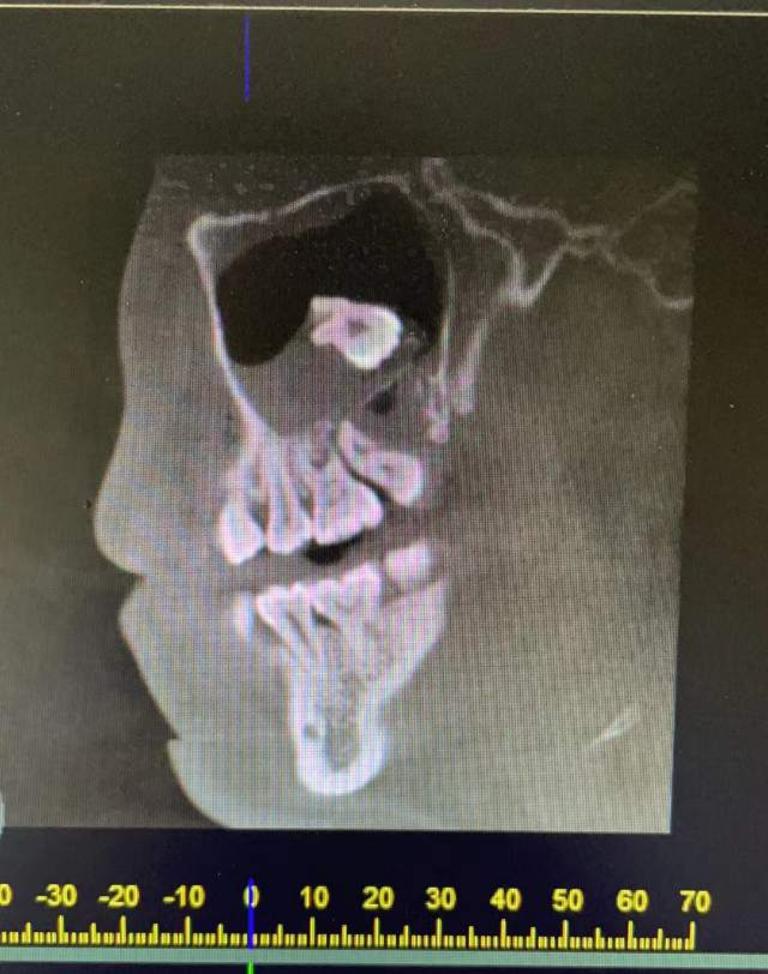

从描述到ct是否为牙源性上颌窦炎

图片尺寸780x1052